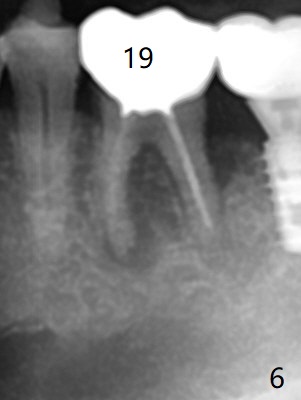

Venopuncture is conducted (Fig.1) for PRF and sticky bone (cortical chip and .5 cc ß-TCP). After use of proximators at #19, cowhorn forceps are applied, resulting in metal crown dislodgement. Since there is distal bone loss, distal socket sheath is contemplated. The tooth is sectioned. When an elevator is inserted between the roots, the distal root is loosened first. The 2 roots are removed, revealing a rounded end septum (Fig.2 S) and a larger distal socket. To avoid osteotomy deviation over the septum, a 12 mm bone trimmer is used, followed by point drill (Fig.3 *). But the lower half of the implant is deviated mesial (Fig.4) with decreased torque (~ 10 Ncm). To overcome this misfortune, the roots should not be removed until osteotomy is finished. Dual zones of bone graft is conducted. Sticky bone is placed until the plateau of the implant with a healing screw in place (Fig.4 * (bone zone)). After placement of a pair abutment, the same bone graft is packed until the margin of the abutment (Fig.5 * (soft tissue zone)). An immediate provisional is fabricated to close the socket with a piece of PRF as well. Fig.6-11 explains why the lower half of the implant deviates to the mesial socket, while Fig.12-16 illustrates how to prevent the deviation. After extraction of #19 (Fig.6,7), the crest of the septum is flattened (Fig.8 arrowhead) to prevent the initial deviation (Fig.9 red line). When a drill reaches a space (a socket, mesial in this case), the drill is deflected to the least resistant area (Fig.10 a bent red line), leading to the implant deviation apically (Fig.11 green). To prevent the apical deviation, therefore, the roots of the affected tooth is temporarily not removed (Fig.12). The osteotomy should not deviates with surgical guide because of similar density between the tooth and the bone (Fig.13). When the osteotomy is finished (Fig.14), the roots are extracted (Fig.15). The implant to be placed should not have deviation (Fig.16 green). The papillae are maintained by the immediate provisional 11 days postop (Fig.17). The incompletely seated abutment at #18 (Fig.5 <) is reseated completely 6 months postop (Fig.18). Crestal bone forms distal to #19 implant. There is no bone loss 4 months and 3 years 1 month post cementation at #19 and 18, respectively (Fig.19,20).